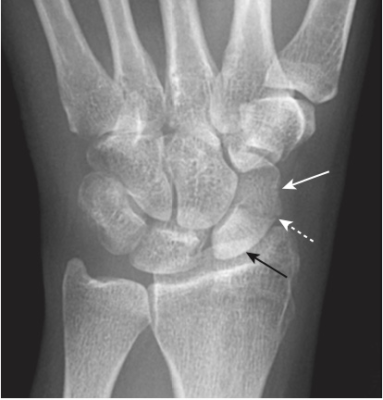

Gãy xương thuyền (Scaphoid fractures)

- Thường gặp

- Nghi ngờ gãy xương thuyền trên lâm sàng nếu đau ở hõm lào giải phẫu (anatomic snuff box) sau khi ngã chống tay.

- Tìm đường thấu quang mỏng trên phim (Tư thế xương thuyền: cổ tay duỗi 30⁰, nghiêng trụ 20⁰) (Hình 14).

- Gãy ngang eo xương thuyền có thể dẫn đến hoại tử vô mạch cực trên xương thuyền.

- Do đặc trưng phân bố mạch máu, gãy ngang eo xương thuyền ở cổ tay làm gián đoạn nguồn cung cấp máu đến cực trên, trong khi phần còn lại của xương cổ tay tiếp tục trải qua quá trình luân chuyển xương, mất khoáng. Kết quả là sự gia tăng tương đối rõ ràng về đậm độ xương của phần trên không được phân nuôi dưỡng so với phần còn lại của xương (Hình 15).